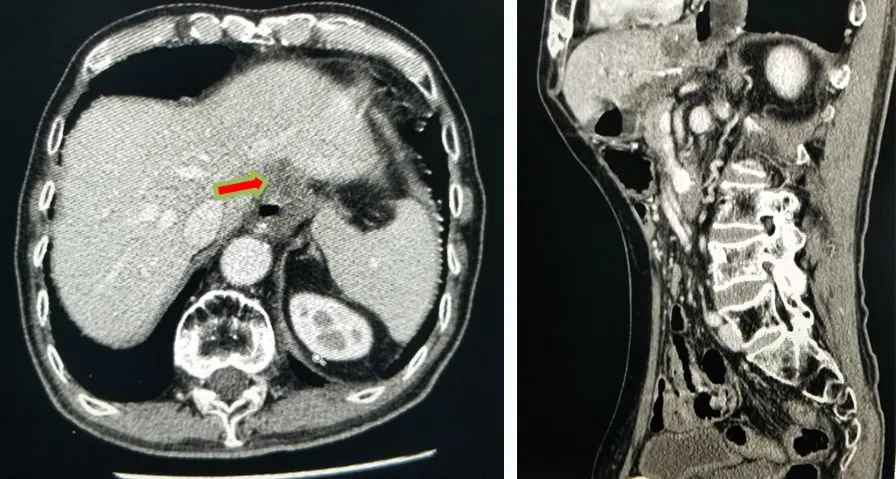

强化CT:1、符合胃部分切除术后,吻合口壁增厚伴食管下段扩张;2、胆囊结石:胆总管结合;3、肠淤张;4、前列腺增大;5、动脉硬化。

PET-CT检查:1、胃癌大部切除术后改变;肝左外叶近包膜下高代谢结节(于临近胃食管吻合口分界欠清),考虑肝转移。2、右肺中上叶多发结节伴代谢轻度增高;双肺间质纤维化;双肺泡性气肿;经根部气管憩室;贫血;动脉硬化;双侧胸膜增厚;右肺门及纵隔内多发淋巴结增生。

△ 2019.7影像学检查

2020-01-08复查腹部CT:与患者前片(2019-7-8)比较显示:食管胃吻合口区低密度病变范围较前缩小。所示腹部其余病变较前未见明显变化,双肺片状高密度影,双侧胸腔积液。

△2020.01腹部CT

2020-08-31复查腹部CT:与患者前片(2020-1-8)比较显示:所示腹部病变较前未见明显变化。双肺高密度影范围较前缩小。

△ 腹部CT 2020.08